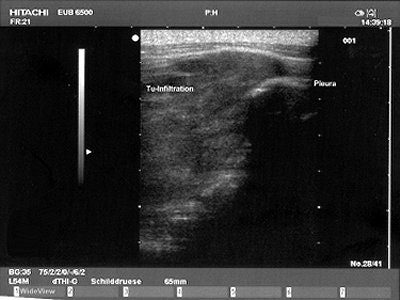

Sonography has no value in the detection of mesothelioma, but it can offer vital information for confirming and fine-tuning the initial diagnosis made with other modalities. Ultrasound is particularly useful for identifying disease changes to the chest wall, diaphragm, or upper chest aperture, explained Dr. Felix Herth from the department of pneumology at the Thoraxklinik in Heidelberg, Germany.

Herth recommended using a highly soluble transducer (5 MHz) to look at pathological findings in the chest wall of mesothelioma patients. In advance stages of the disease, tumor infiltration of the lung tissue will appear as echo-poor, oblong structures along the ventilated lung. Pleural metastases are also echo-poor, or moderately echo-close, and present as roundish, small, knotty, or laminar processes with irregular delimitation.

| A Brustwand echocardiogram depicting infiltrating carcinoma. |

"Pleural mesothelioma presents sonographically as an irregularly limited, echo-poor, knotty, or planar widening along the pleura," Herth wrote in Lung Cancer. "An increase in the pleural thickness, however, suggests the likelihood of malignancy. A widening of the pleura of more than 1 cm is considered highly indicative of the presence of malignant tumor" (August 2004, Vol. 45:1 supplement, pp. S63-67).